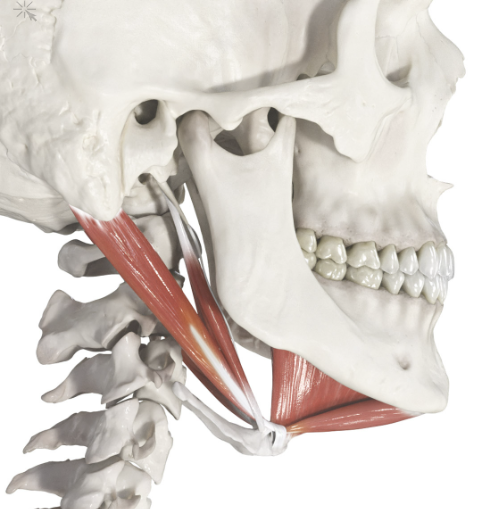

Is it stupid to do a surgery that shortens the suprahyoid muscle/musscles to move the hyoid bone up?